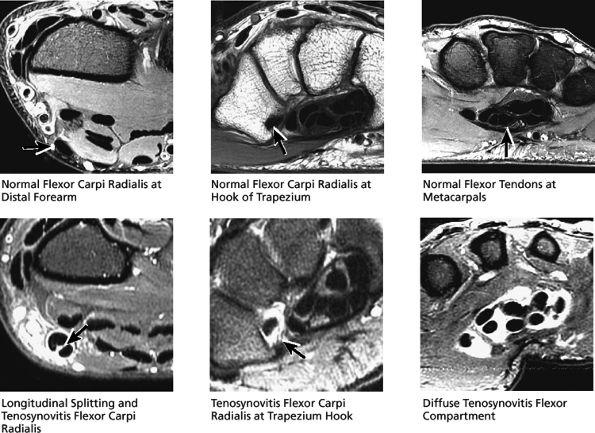

FIGURE 10.4 ● FLEXOR CARPI RADIALIS The flexor carpi radialis lies radial to the palmaris longus and ulnar to the pronator teres throughout its course. It contributes to flexion and abduction of the wrist. Distal flexor carpi radialis tendon rupture, usually occurring after a fall on the outstretched hand, can clinically mimic a scaphoid fracture.

FIGURE 10.32 ● Normal axial anatomy. (A) Fractures of the hook of the hamate, commonly occult on plain films, are easily visualized on axial MR images through the hamate. (B) The flexor carpi radialis is visualized cradled by the hook of the trapezium. This is a common location for tenosynovitis and tendinosis of the flexor carpi radialis tendon. (C) The thenar muscles (abductor and flexor pollicis brevis) are visualized volar to the radial aspect of the distal carpus. Median neuritis should be suspected when selective fatty atrophy or denervation of the thenar muscles is visualized. (D) The median nerve within the carpal tunnel may display evidence of median neuritis, such as increased signal or enlargement. A mass lesion of the carpal tunnel at this level may cause mass effect within the carpal tunnel and impinge the median nerve. (E) The pisotriquetral joint is a common location for severe degenerative arthritis and synovitis, associated with significant ulnar-sided pain. (F) The extensor pollicis longus crosses obliquely dorsal to the extensor pollicis longus and brevis tendons. This is a not uncommon location for tears of the extensor pollicis longus tendon. (G) The scapholunate articulation is a common location for ganglion cysts, usually found directly dorsal to the scapholunate ligament. Even small dorsal ganglion cysts in this location can be exquisitely tender and painful. Often, a small neck of fluid signal extends from the dorsal ganglion cyst back toward the scapholunate ligament, and in certain cases a small perforation of the scapholunate ligament can be suggested. (H) The extensor pollicis brevis and abductor pollicis longus tendons are located lateral to the distal radius. Tendinosis and tenosynovitis of these tendons is known as de Quervain's stenosing tenosynovitis. (I) Not uncommonly the extensor carpi ulnaris tendon is subluxed over the ulnar styloid, particularly when the patient is supinated, with the ulnar styloid pointing dorsally. This is not necessarily an abnormal finding, particularly when the extensor carpi ulnaris tendon otherwise appears normal. (J) The triangular shape of the TFC complex is best appreciated on axial images, with the apex of the triangle attaching at the ulnar styloid and the broader base of the triangle attaching at the radius. (K) The distal radioulnar joint is examined in the axial plane to view the alignment of the radius with respect to the ulna. The ulna lies within the concave groove in the medial aspect of the radius called the sigmoid notch, and the two bones lie grossly in the same plane. Mild apparent dorsal shift of the ulna with respect to the radius is normal when the wrist is scanned in full pronation (the ulnar styloid pointing ulnar-volar). (L) When the triangular fibrocartilage is torn, or if there is a displaced fracture at the base of the ulnar styloid, the distal radial ulnar joint may become somewhat destabilized, ultimately resulting in degenerative arthrosis and synovitis. Another cause of distal radioulnar joint degenerative change is the ulnar impingement syndrome, in which a short ulna erodes the ulnar aspect of the distal radius.